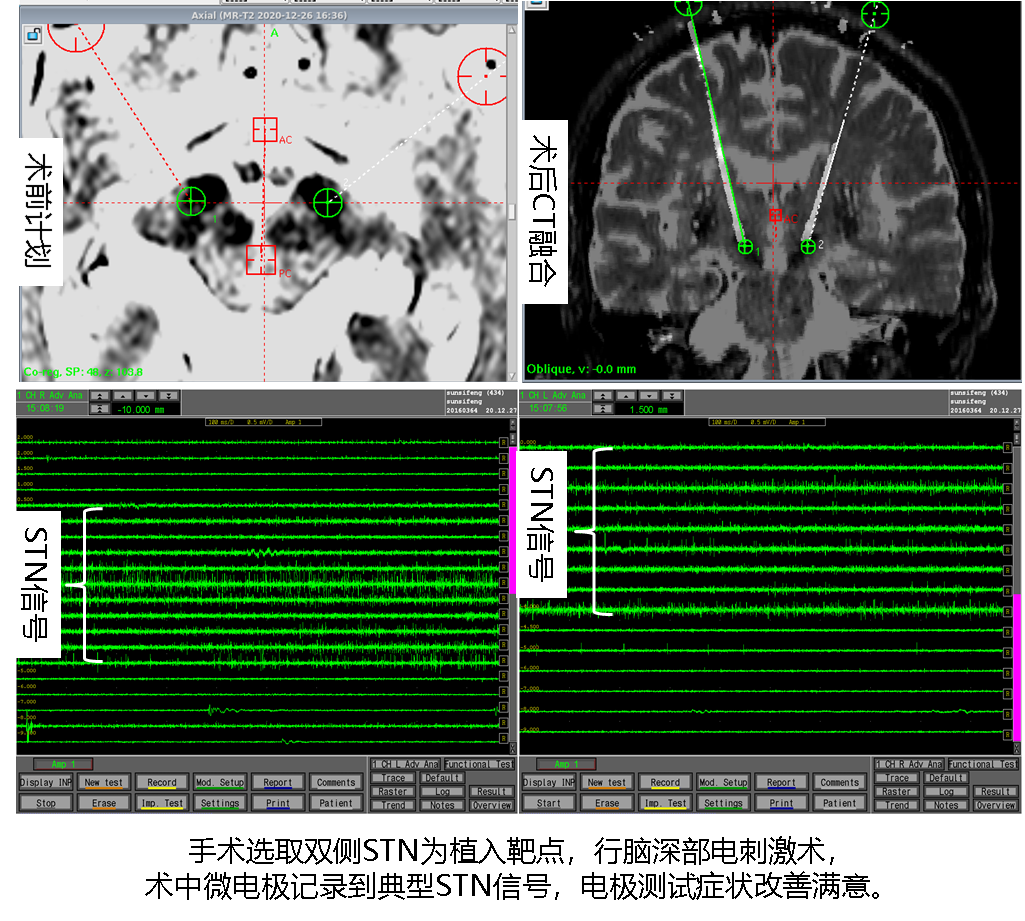

患者入院第一天进一步完善术前各项准备,入院第二天上午在局麻下行胸主动脉覆膜支架植入术,手术顺利。下午随即行DBS手术,手术选取双侧STN为植入靶点;术中微电极记录到典型STN信号,术中电极刺激测试患者肢体活动灵活性较刺激前明显改善,肌张力降低,震颤症状得到明显缓解,未见不可耐受的副反应;术后患者即可开机行脑深部电刺激治疗,运动迟缓等症状得到明显改善,复查颅脑CT可见电极按术前计划精准植入STN靶点,胸主动脉CTA可见胸主动脉瘤完全闭塞,支架位置满意,血管充盈良好。